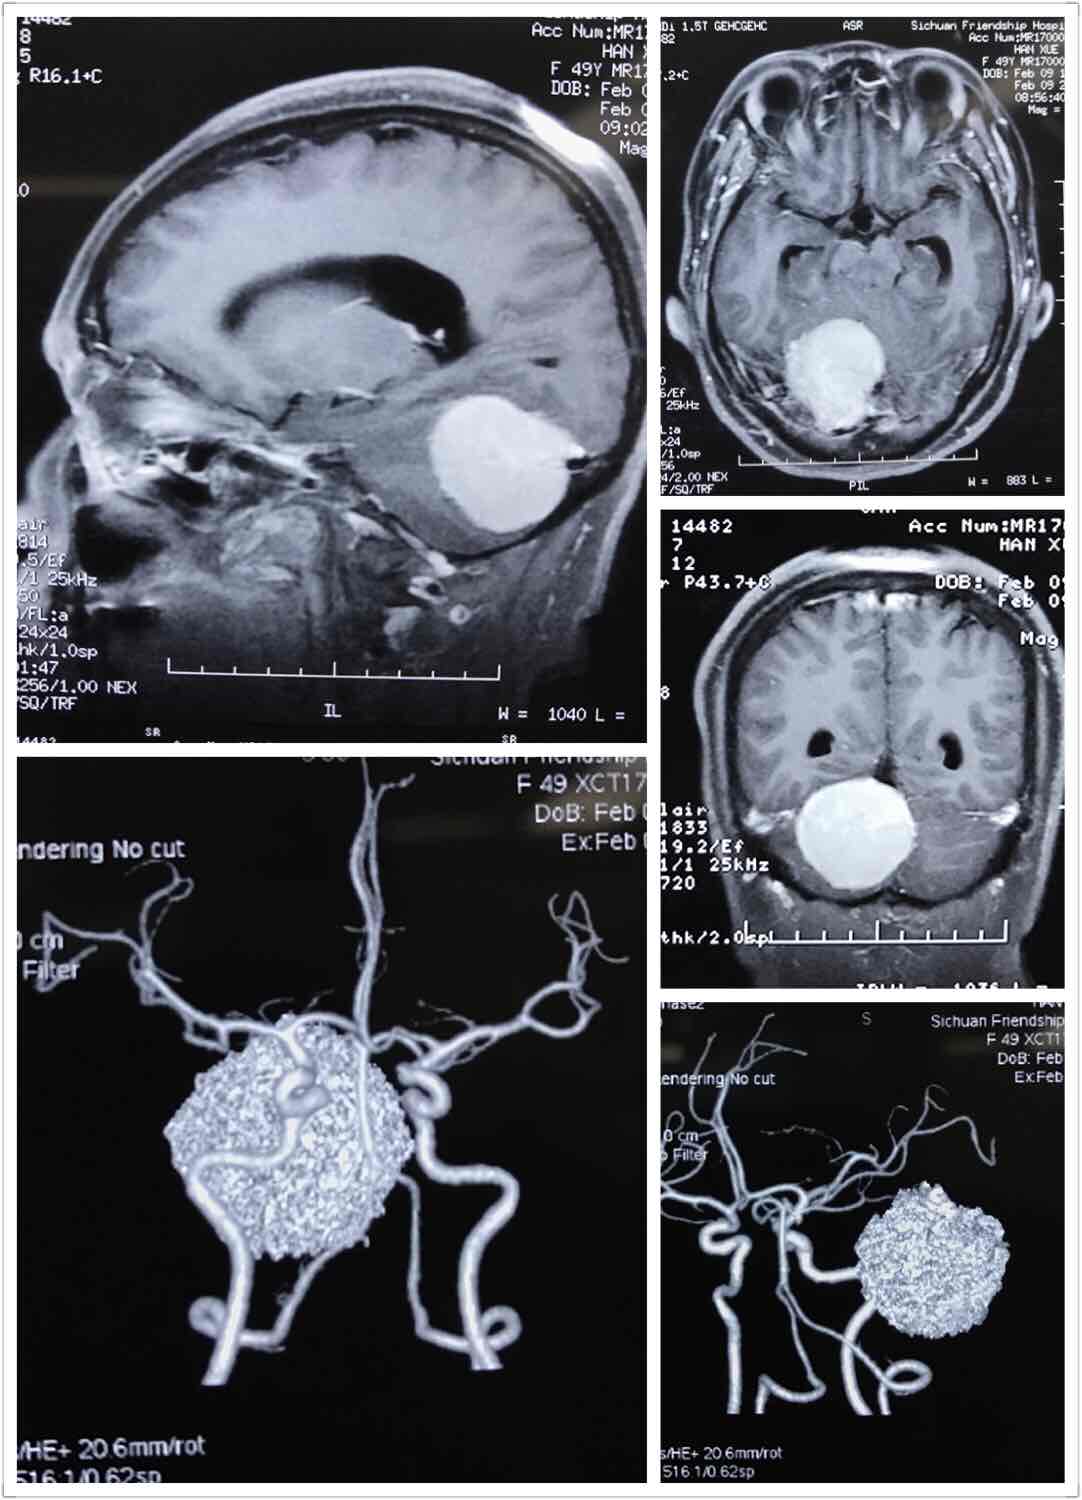

右侧小脑幕脑膜瘤

图片尺寸1082x1500